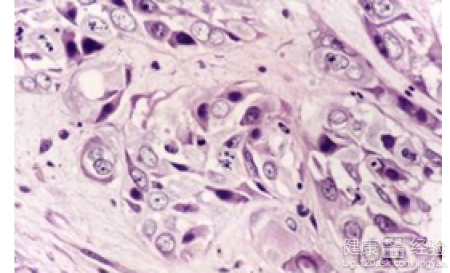

高熱驚厥是一個比較常見的小兒科的疾病。孩子往往在體溫升高大於等於三十九攝氏度的時候發生驚厥的症狀。需要進一步的檢查的,而且需要進一步排除病人是沒有顱內感染的問題。而且導致驚厥的器質性的疾病和其他的代謝性疾病也是需要積極的治療的。高熱驚厥是一個需要解決治療的疾病,有過高熱驚厥出水痘溫度該如何控制呢?下面一起看看。

1有過高熱驚厥的病人,如果在出水痘的時候,那麼往往會有體溫比較高的症狀,那麼需要積極的控制溫度的溫度。可以喝板藍根顆粒的,可以物理降溫的。而且在水痘初發的一兩天可用一種抗水痘藥物治療,積極的去緩和病情。